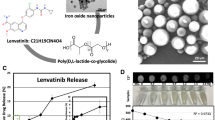

Preparation of PH1/HGFK1 Nanoparticles

The PEG3350-PEI600-CyD backbone was synthesized according to our previous study [13, 14]. In brief, polyethylene glycol (PEG3350, 250 mg) was dissolved in dimethyl sulfoxide (DMSO) and mixed with 1,10-carbon-yldiimidazole (CDI, 40 mg) under nitrogen atmosphere. The mixture was then added to the phosphate buffer solution (PBS) containing PEI600-CyD (240 mg) to obtain PEG3350-PEI600-CyD powder. Finally, H1 was mixed with PEG3350-PEI600-CyD at a molar ratio of 1:1 to obtain Peglated-H1 (PH1). To prepare PH1/HGFK1 polyplexes, PH1 and HGFK1 plasmids were mixed at an N/P ratio of 20:1 in the same volume. The polyplexes were stabilized for 10 min at room temperature before injection.

To investigate the anti-tumor activity of HGFK1, we generated the purified recombinant HGFK1. The cell viability was significantly decreased in HepG2 and ML-1 cells after treatment with HGFK1 in a dose-dependent manner (P < 0.05). However, no significant change was observed in LO2 cells after treatment with HGFK1 (P > 0.05, Fig. 1). As shown in Fig. 2, flow cytometry showed that compared with the control group, the apoptotic rate of HepG2 cells was markedly increased in the HGFK1 group (4.91 ± 0.18% vs. 11.13 ± 0.8%, P < 0.001). Similarly, the apoptotic rates in the ML-1 cells were markedly increased about 2 folds in the HGFK1 group than in the control group (P < 0.05).

HGFK1 inhibited HC cell proliferation in vitro. MTT assay showed the cell viability of HepG2, ML-1, and LO2 cells treated with different doses of HGFK1 for 48 h. All data were presented as the mean ± SD from at least three independent experiments. *P < 0.05, **P < 0.01, ***P < 0.001 vs. the 0 µg/ml group

Gene therapy cannot continue to play an effective role in cells because it is easy to be degraded by ribozymes with the poor ability of endocytosis and endosome escape. In our previous study, a new method is synthesized by β-cyclodextrin crosslinked low molecular weight polyethyleneimine (PEI) grafted folate positron polymer (PEI-CyD-FA, named H1). The vector can concentrate and package the plasmid into spherical nanoparticles with a diameter of about 100 nm. Subsequent animal and cell experiments have confirmed that the vector has the characteristics of low toxicity, high transduction efficiency, and folate ligand targeting. PEG is coupled to H1 to form a new carrier, which is named PH1 after being mixed with H1 in equal proportion. HGFK1 is transduced to explore its anti-HCC effect.